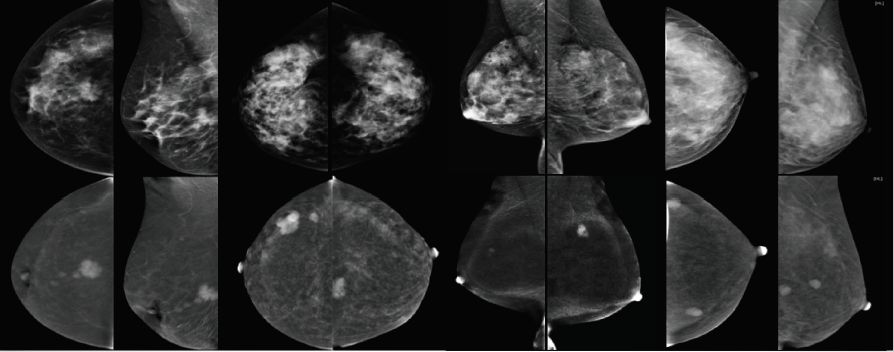

等到发现乳腺癌“敌人”,再行歼灭,自然是下策。上策是揪出潜伏的“敌人”,在其未出手前,兵不血刃,一招克敌。所以随着高科技的发展以及人们对体检筛查意识的增强,我们往往会在单位体检或个人体检单上,看到“乳腺X光(钼靶)检查”这一选项。乳房x线(钼靶)检查是检查乳房是否患有乳腺癌的x光照片,有助于在乳腺癌扩散到身体其他部位之前及早发现它。

上海美中嘉和的GE乳腺钼靶,引领乳腺摄影进入功能成像时代。其能谱增强技术,大幅提高乳腺诊断的敏感性和特异性